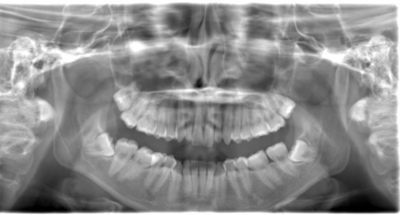

CASE 3

基本情報

| 年齢・性別 | 20代・男性 |

| 主訴 | 左下親知らず抜きたい |

| 親知らずのはえ方 | 半埋伏 |

| 抜歯期間 | 30分 |

| 抜歯費用 | 約2,500円(保険内) 別途CT撮影で3,000円 |

| 抜歯内容 | 左下の半埋伏親知らず抜歯 |